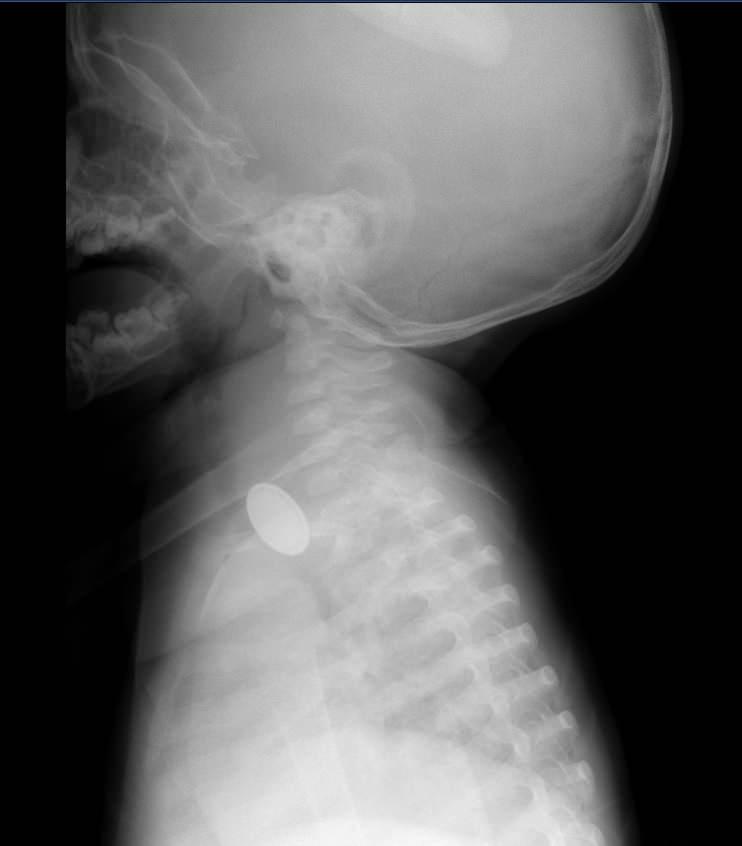

Kayseri’de 15 aylık bebeğin yemek borusuna pil ve lego parçası kaçtı

Bir süre sonra A.Y.Ç.'nin yutma güçlüğü çektiğini gören Tuğba Yılmaz, Kayseri Şehir Hastanesi'ne başvurdu.